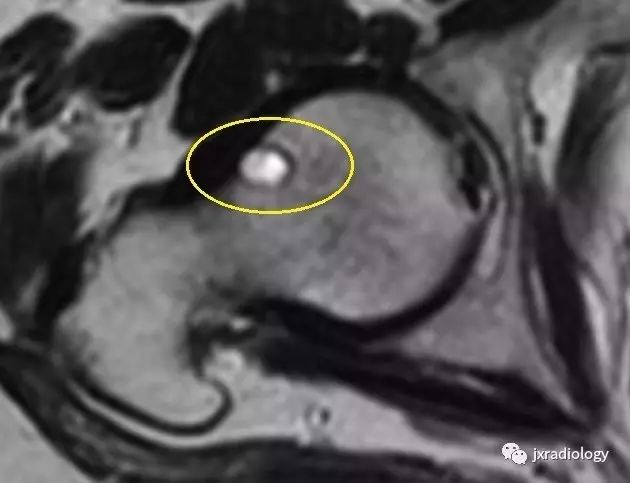

影像表现:X 线平片上表现为伴有清晰薄层硬化缘的环形(囊状)透亮区,CT 上表现为圆形 或类圆形的皮质下局灶性骨质缺损,周围见薄层硬化带环绕,边缘锐利,部分较大病灶在病灶层面或上下相邻、层面上前方显示皮质与病灶相通的局部裂隙样缺损病灶,最大径线通常小于 10 mm;MRI 示病灶在 T1WI 上呈低信号,在 T2WI 上呈均匀或不均匀高信号。

鉴别诊断:X 线平片对股骨颈疝窝具有初步诊断价值;依据典型的CT和/或MRI影像学表现,对股骨颈疝窝多可以作出准确的诊断。需要与骨内的腱鞘囊肿相鉴别:是一相邻关节的囊性病变,内衬滑膜细胞并含有粘液样物质,有时液体内蛋白质较高在T1W 上信号趋向升高。